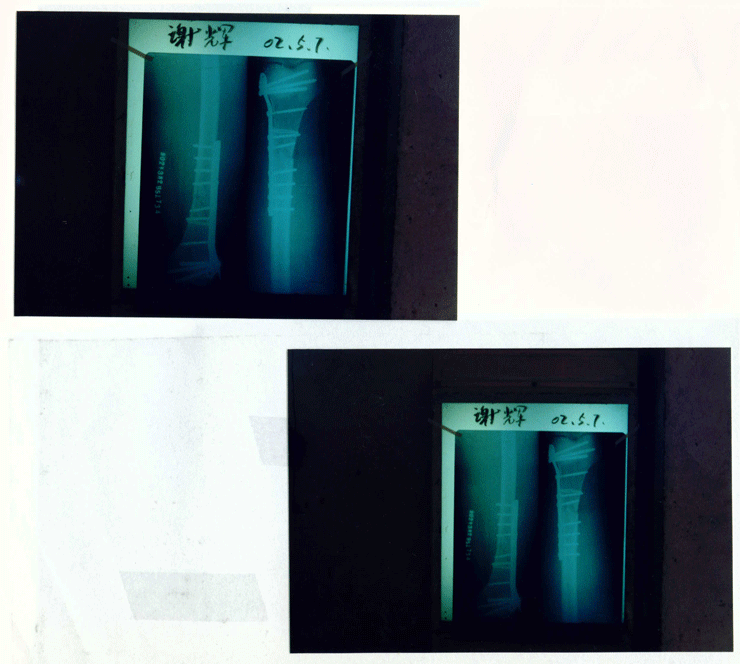

谢辉(左膝关节)

2002.5.7

左股骨下段骨折术后膝关节粘连65天

X光图